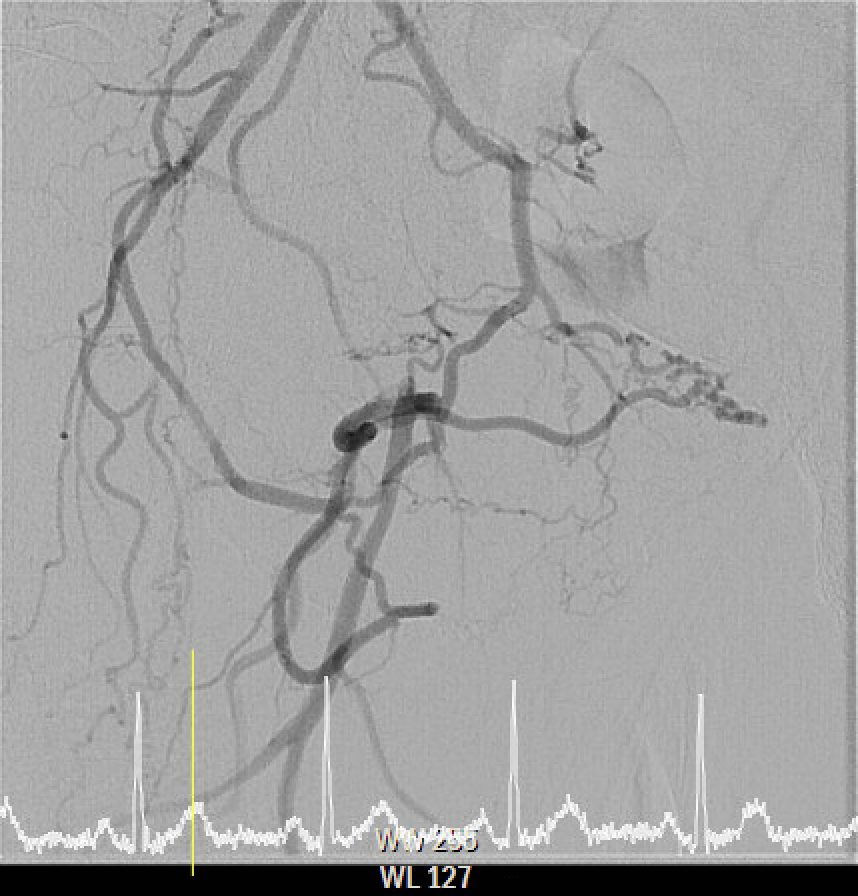

The procedure utilized a hybrid retrograde and antegrade approach. Retrograde access was established via a micropuncture kit under angiography guidance into the distal Superficial Femoral Artery (dSFA), but wiring attempts failed due to an intervening aneurysm, necessitating a switch to the antegrade route from the left brachial artery. A wire escalation technique, assisted by a microcatheter, successfully crossed the extensive CTO, and was met with retrograde microcatheter and externalized via the dSFA puncture site (retrograde access), establishing through-and-through wire access. Following initial balloon predilation and IVUS confirmation of diffuse thrombus, extensive angioplasty was performed. Definitive treatment involved deploying multiple overlapping GORE¢ç VIABAHN¢ç Endoprosthesis diameters (from 6mm to 8mm) from the dSFA proximally to the pEIA via left femoral access, effectively treating the long occlusion and excluding the aneurysm. A COOK Zilver Flex iliac stent reinforced the proximal landing zone. The stented segment was rigorously post-dilated up to 12 atm. The procedure concluded with a Drug-Eluting Balloon (DEB) PTA (BOSTON Ranger Paclitaxel-Coated PTA Balloon Catheter) to the dSFA to mitigate restenosis in the non-stented region. Final angiography confirmed good flow without distal embolization.

Case Summary

The angiography confirmed extensive Chronic Total Occlusion (CTO) of the right External Iliac Artery (EIA), Common Femoral Artery (CFA), and proximal Superficial Femoral Artery (SFA). The limb's circulation was critically dependent on collateral flow: the Deep Femoral Artery (DFA) was patent and supplying the distal SFA. Distally, a 50% stenosis was noted in the Popliteal Artery, but the Below-the-Knee (BTK) arteries were patent.